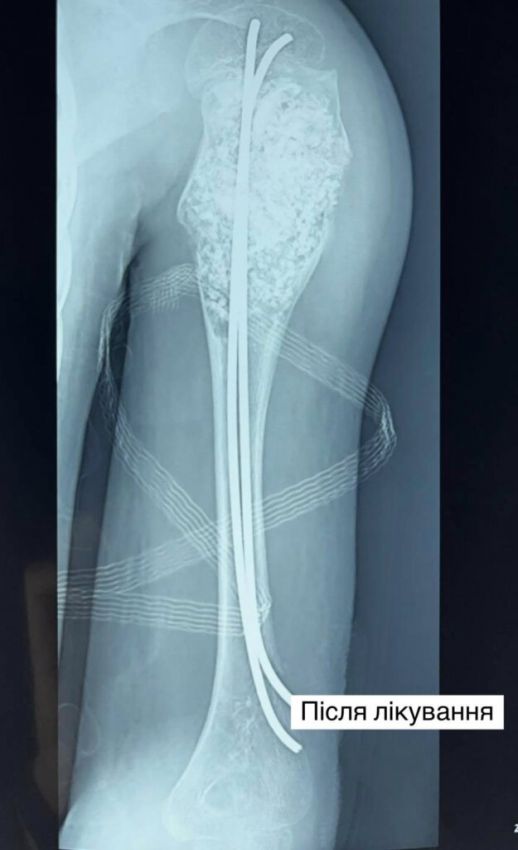

Після усіх обстежень ортопеди-травматологи лікарні провели складну операцію: виконали внутрішню кісткову резекцію – видалили пухлину розміром 9 см на 4 см та замістили дефект кістковими аллотрансплантатами. А також провели металоостеосинтез кістки двома гнучкими титановими стержнями, щоб уникнути повторних переломів. У післяопераційному періоді рука дитини була іммобілізована тільки косинковою пов’язкою, без використання важкої та громіздкої гіпсової пов’язки.

Зараз Іван проводить активну реабілітацію, відновлює рухи у плечовому суглобі та силу м’язів, його кістка має повністю відновити свою структуру та міцність. Нарешті хлопчик зможе повернути собі звичне дитинство – без страху перед кожним рухом.